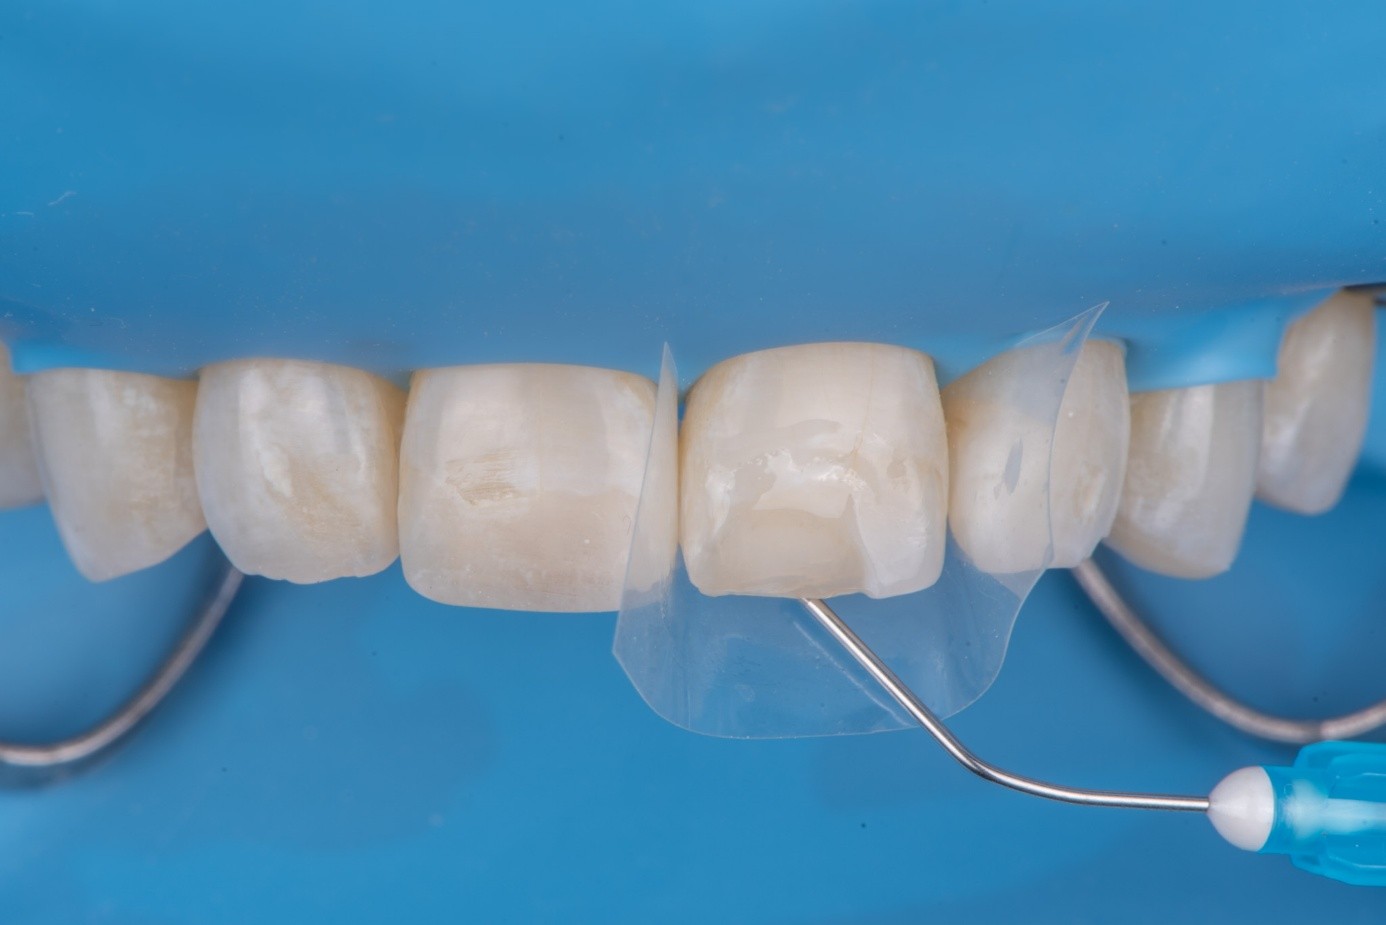

After achieving rubber dam isolation, the fractured composite segment was first air-abraded with aluminum oxide particles to clean and roughen the surface. It was then etched with phosphoric acid for 60 seconds, rinsed, dried, and treated with silane to enhance chemical adhesion (Figure 18 through Figure 20).8,9

The tooth surface was similarly air-abraded to remove biofilm and aged resin remnants, then selectively etched with phosphoric acid. Silane was applied intraorally to the exposed composite surface to promote bonding between the old and new composite layers.10 Following this, a universal bonding agent was applied to both the tooth surface and the fractured composite segment (Figure 21 through Figure 24).

(21.) Intraoral view after rubber dam isolation, showing prepared surfaces: both sandblasted and etched, with silanization applied only to the composite surface, ready for reattachment.

Figure 21

(22.) Intraoral view after rubber dam isolation, showing prepared surfaces: both sandblasted and etched, with silanization applied only to the composite surface, ready for reattachment.

Figure 22

(23.) Intraoral view after rubber dam isolation, showing prepared surfaces: both sandblasted and etched, with silanization applied only to the composite surface, ready for reattachment.

Figure 23

(24.) Intraoral view after rubber dam isolation, showing prepared surfaces: both sandblasted and etched, with silanization applied only to the composite surface, ready for reattachment.

Figure 24